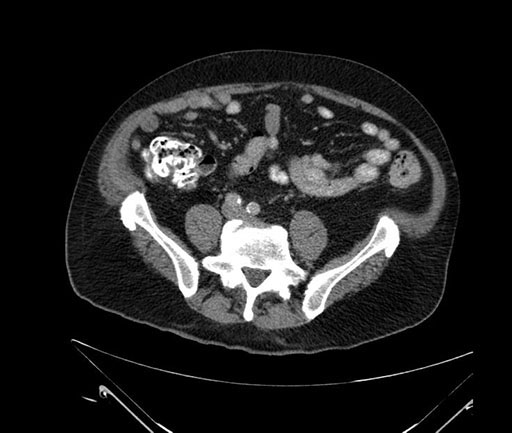

Coronal - stented